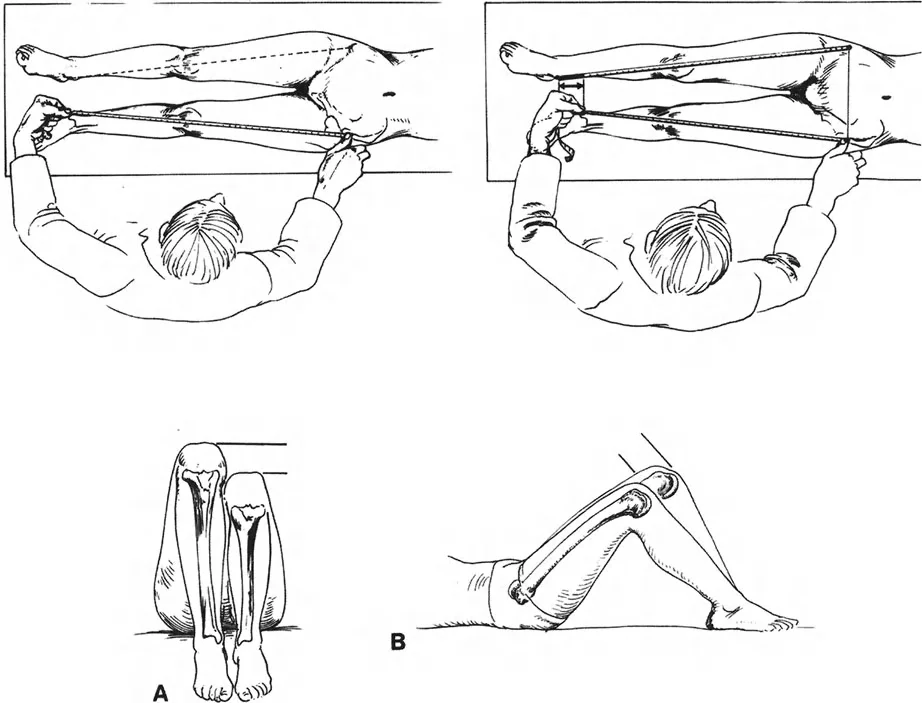

نصيحة سريرية: لتحديد ما إذا كان القصر في الفخذ أو الساق، قم بإجراء اختبار جالياتزي (Galeazzi test). مع استلقاء المريض على ظهره، وثني الوركين بزاوية 45 درجة، وثني الركبتين بزاوية 90 درجة مع وضع القدمين مسطحتين على الطاولة، لاحظ ارتفاع الركبتين. إذا كانت إحدى الركبتين منخفضة، فإن الساق قصيرة. إذا كانت إحدى الركبتين تبرز أقل إلى الأمام، فإن الفخذ قصير.